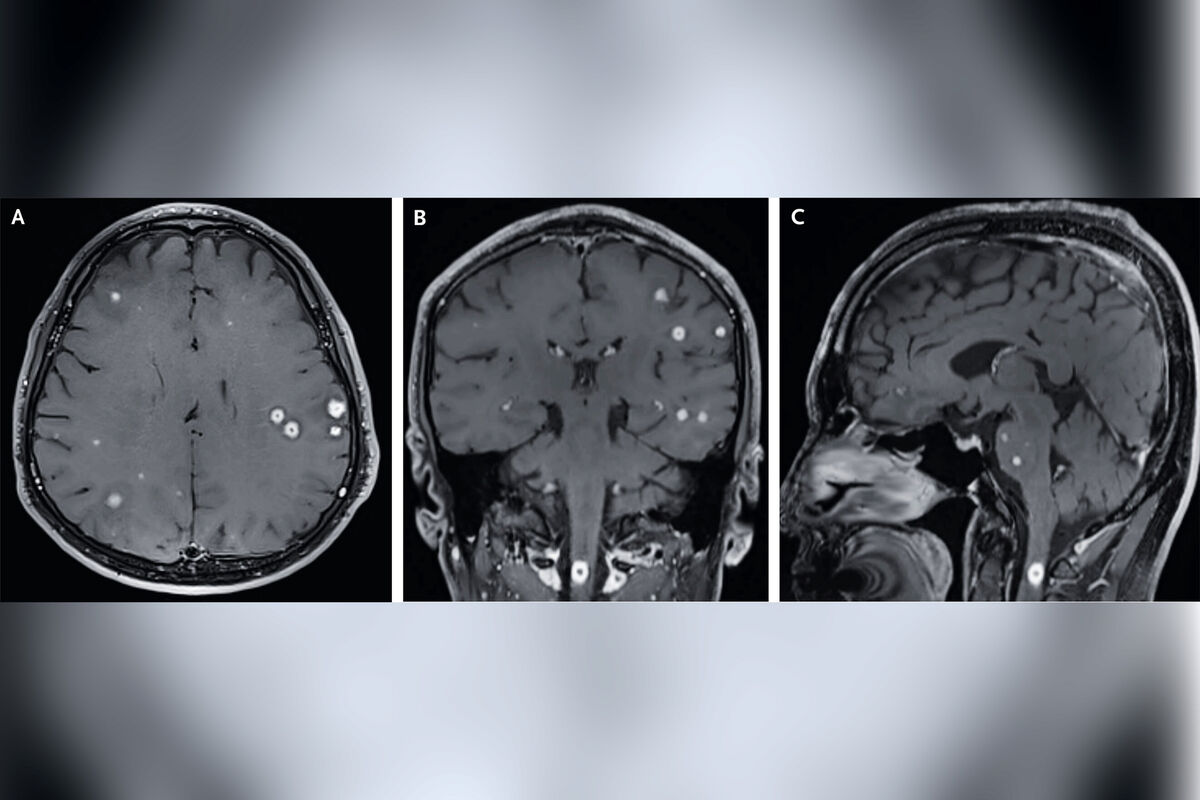

В отделении неотложной помощи одной из больниц Южной Кореи врачи столкнулись с необычной и тревожной картиной на магнитно-резонансной томограмме (МРТ) мозга пациента. Вместо привычных структур на снимке были видны многочисленные яркие очаги поражения, которые сформировали узор, напоминающий «звездное небо». Этот впечатляющий, но пугающий паттерн оказался проявлением редкой и опасной формы туберкулеза. Загадочный случай, как сообщает Ars Technica, был описан южнокорейскими врачами в последнем выпуске издания New England Journal of Medicine.

Пациент, 57-летний мужчина, ранее проходивший лечение от туберкулеза легких, обратился за медицинской помощью с жалобами на необъяснимые головные боли, боль в шее и покалывание в правой руке, которые продолжались две недели. Проведенные МРТ и компьютерная томография (КТ) четко выявили причину его состояния: редкие узлы и очаги поражения, известные как туберкулемы, были рассеяны не только в легких, но и по всей центральной нервной системе (ЦНС). Эти поражения были обнаружены в обоих полушариях головного мозга, базальных ганглиях, мозжечке, стволе мозга и верхнем отделе спинного мозга.

Пациенту был назначен интенсивный курс противотуберкулезных антибиотиков в сочетании с противовоспалительным препаратом. Благодаря своевременной и агрессивной терапии состояние мужчины стало постепенно улучшаться. Уже через месяц он почувствовал себя значительно лучше. Спустя 18 месяцев симптомы полностью исчезли, а контрольная МРТ головного мозга показала полное разрешение очагов поражения и нормальную картину.